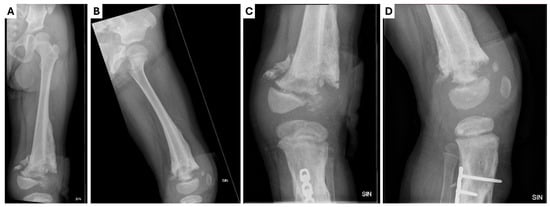

One week after discharge, the patient was playing on the couch at home when her leg got stuck, causing instability and the dislocation of the external fixator (Figure 3). She was admitted acutely with purulent discharge from the wounds. We evacuated the rods of the external fixator from the bone and sent the biological material for microbiological examination. Blood cultures were negative for microflora and no signs of active inflammation were noticed in the laboratory tests. The wound was cleaned and immobilized with a plaster cast. Prophylactic clindamycin at 200 mg three times a day was prescribed along with ibuprofen per os. The patient was discharged on the third post-operative day. A planned follow-up in three weeks was recommended.

Figure 3.

Radiological examinations of the left leg showing the dislocation of one of the external fixators (yellow circle) in the (A) X-ray anterior–posterior projection; (B) X-ray lateral projection.